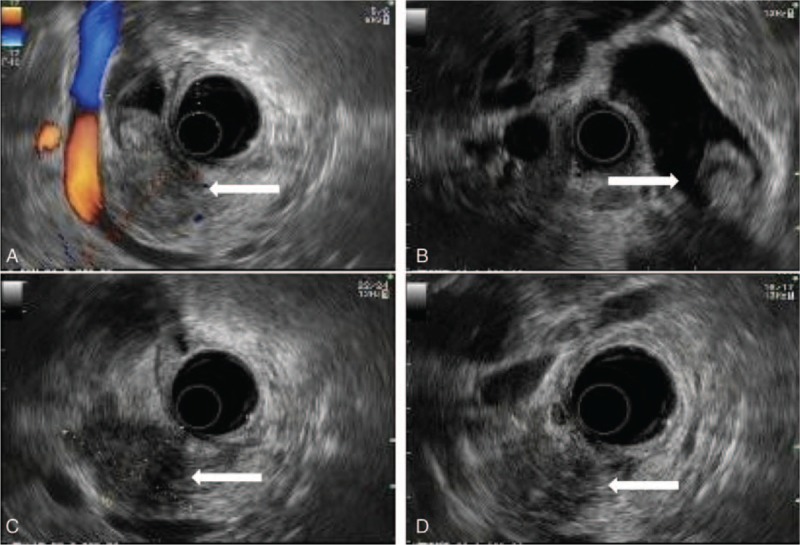

The endoscopic ultrasonography and abdominal computed tomography scans prior to surgery displayed a mass measuring 4.0 × 3.5 cm located in the distal CBD, which had penetrated from the bile duct to the pancreas, with the presence of marked dilatation of the proximal CBD, gallbladder, and right and left common hepatic and intrahepatic ducts (Figs. 1 and 2). No lymphadenopathy was noted in the upper abdomen.